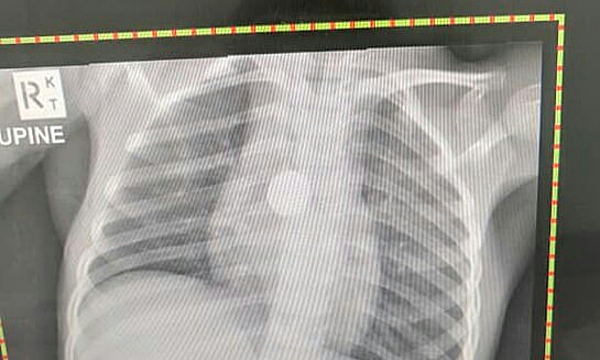

Vào cuối tháng 3, Yamazaki bị sốt, nôn mửa, sụt cân nghiêm trọng và được đưa đến Bệnh viện Casey để cấp cứu. . Chụp X quang khiến bác sĩ ngạc nhiên: một cục pin tròn bị kẹt trong cổ họng của em bé, ngăn không cho thức ăn vào bụng và ăn mòn các bộ phận xung quanh.

Hình ảnh X-quang cho thấy pin bị mắc kẹt trong cổ họng. Ảnh: CN